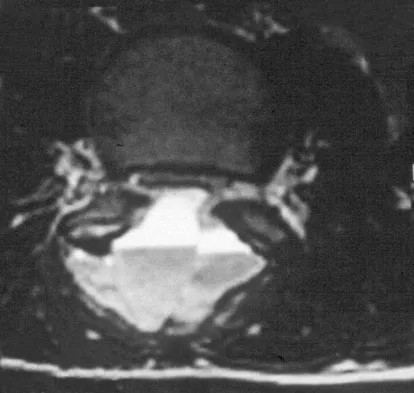

A 44-year-old woman has had lower extremity dysesthesias, urinary incontinence, and has been unable to walk for the past 2 days. She reports no pain or history of trauma. She notes that 3 weeks ago she missed work for 2 days because of back pain, but it resolved with rest. Examination shows decreased or absent sensation below the knees, no motor function below the knees, and decreased rectal tone. Catheterization results in a postvoid residual of 2,000 mL. Plain radiographs and MRI scans without contrast are shown in Figures 1a through 1d. What is the next most appropriate step in management?

Explanation

The patient has had a clear and sudden onset of a profound neurologic deficit. The radiographic studies suggest a lesion in the conus medullaris that appears to be intradural and intramedullary. MRI, with and without contrast, will best evaluate this mass further. The addition of gadolinium allows further evaluation of vascularity and the extent of the lesion. Eichler ME, Dacey RG: Intramedullary spinal cord tumors, in Bridwell KH, Dewald RL (eds): The Textbook of Spine Surgery, ed 2. Philadelphia, PA, Lippincott-Raven, 1997, vol 2, pp 2089-2116.